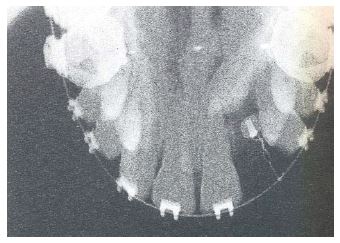

peetunud lõike- või silmahambad; hambad on küll olemas kuid nad on peetunud

kui puudub lõike- või silmahammas või rohkem kui üks hammas lõualuu ühel poolel